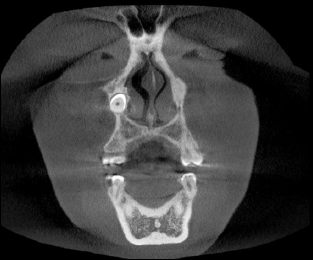

En la exploración intraoral observamos ausencia clínica del canino superior derecho y un diastema entre los dientes 12 y 14 (figura 1). Tras el estudio de la imagen panorámica (figura 2), se observa que el canino derecho superior se encuentra invertido y ubicado en la apófisis ascendente maxilar. Debido a la ubicación ectópica del diente, se solicita una tomografía axial computarizada de la estructura maxilofacial (TAC) (figura 3). Con esta ayuda diagnóstica se tendría mayor información sobre la ubicación exacta del canino derecho superior invertido (diente 13), situado en la apófisis ascendente maxilar, con respecto a las estructuras próximas o cercanas.